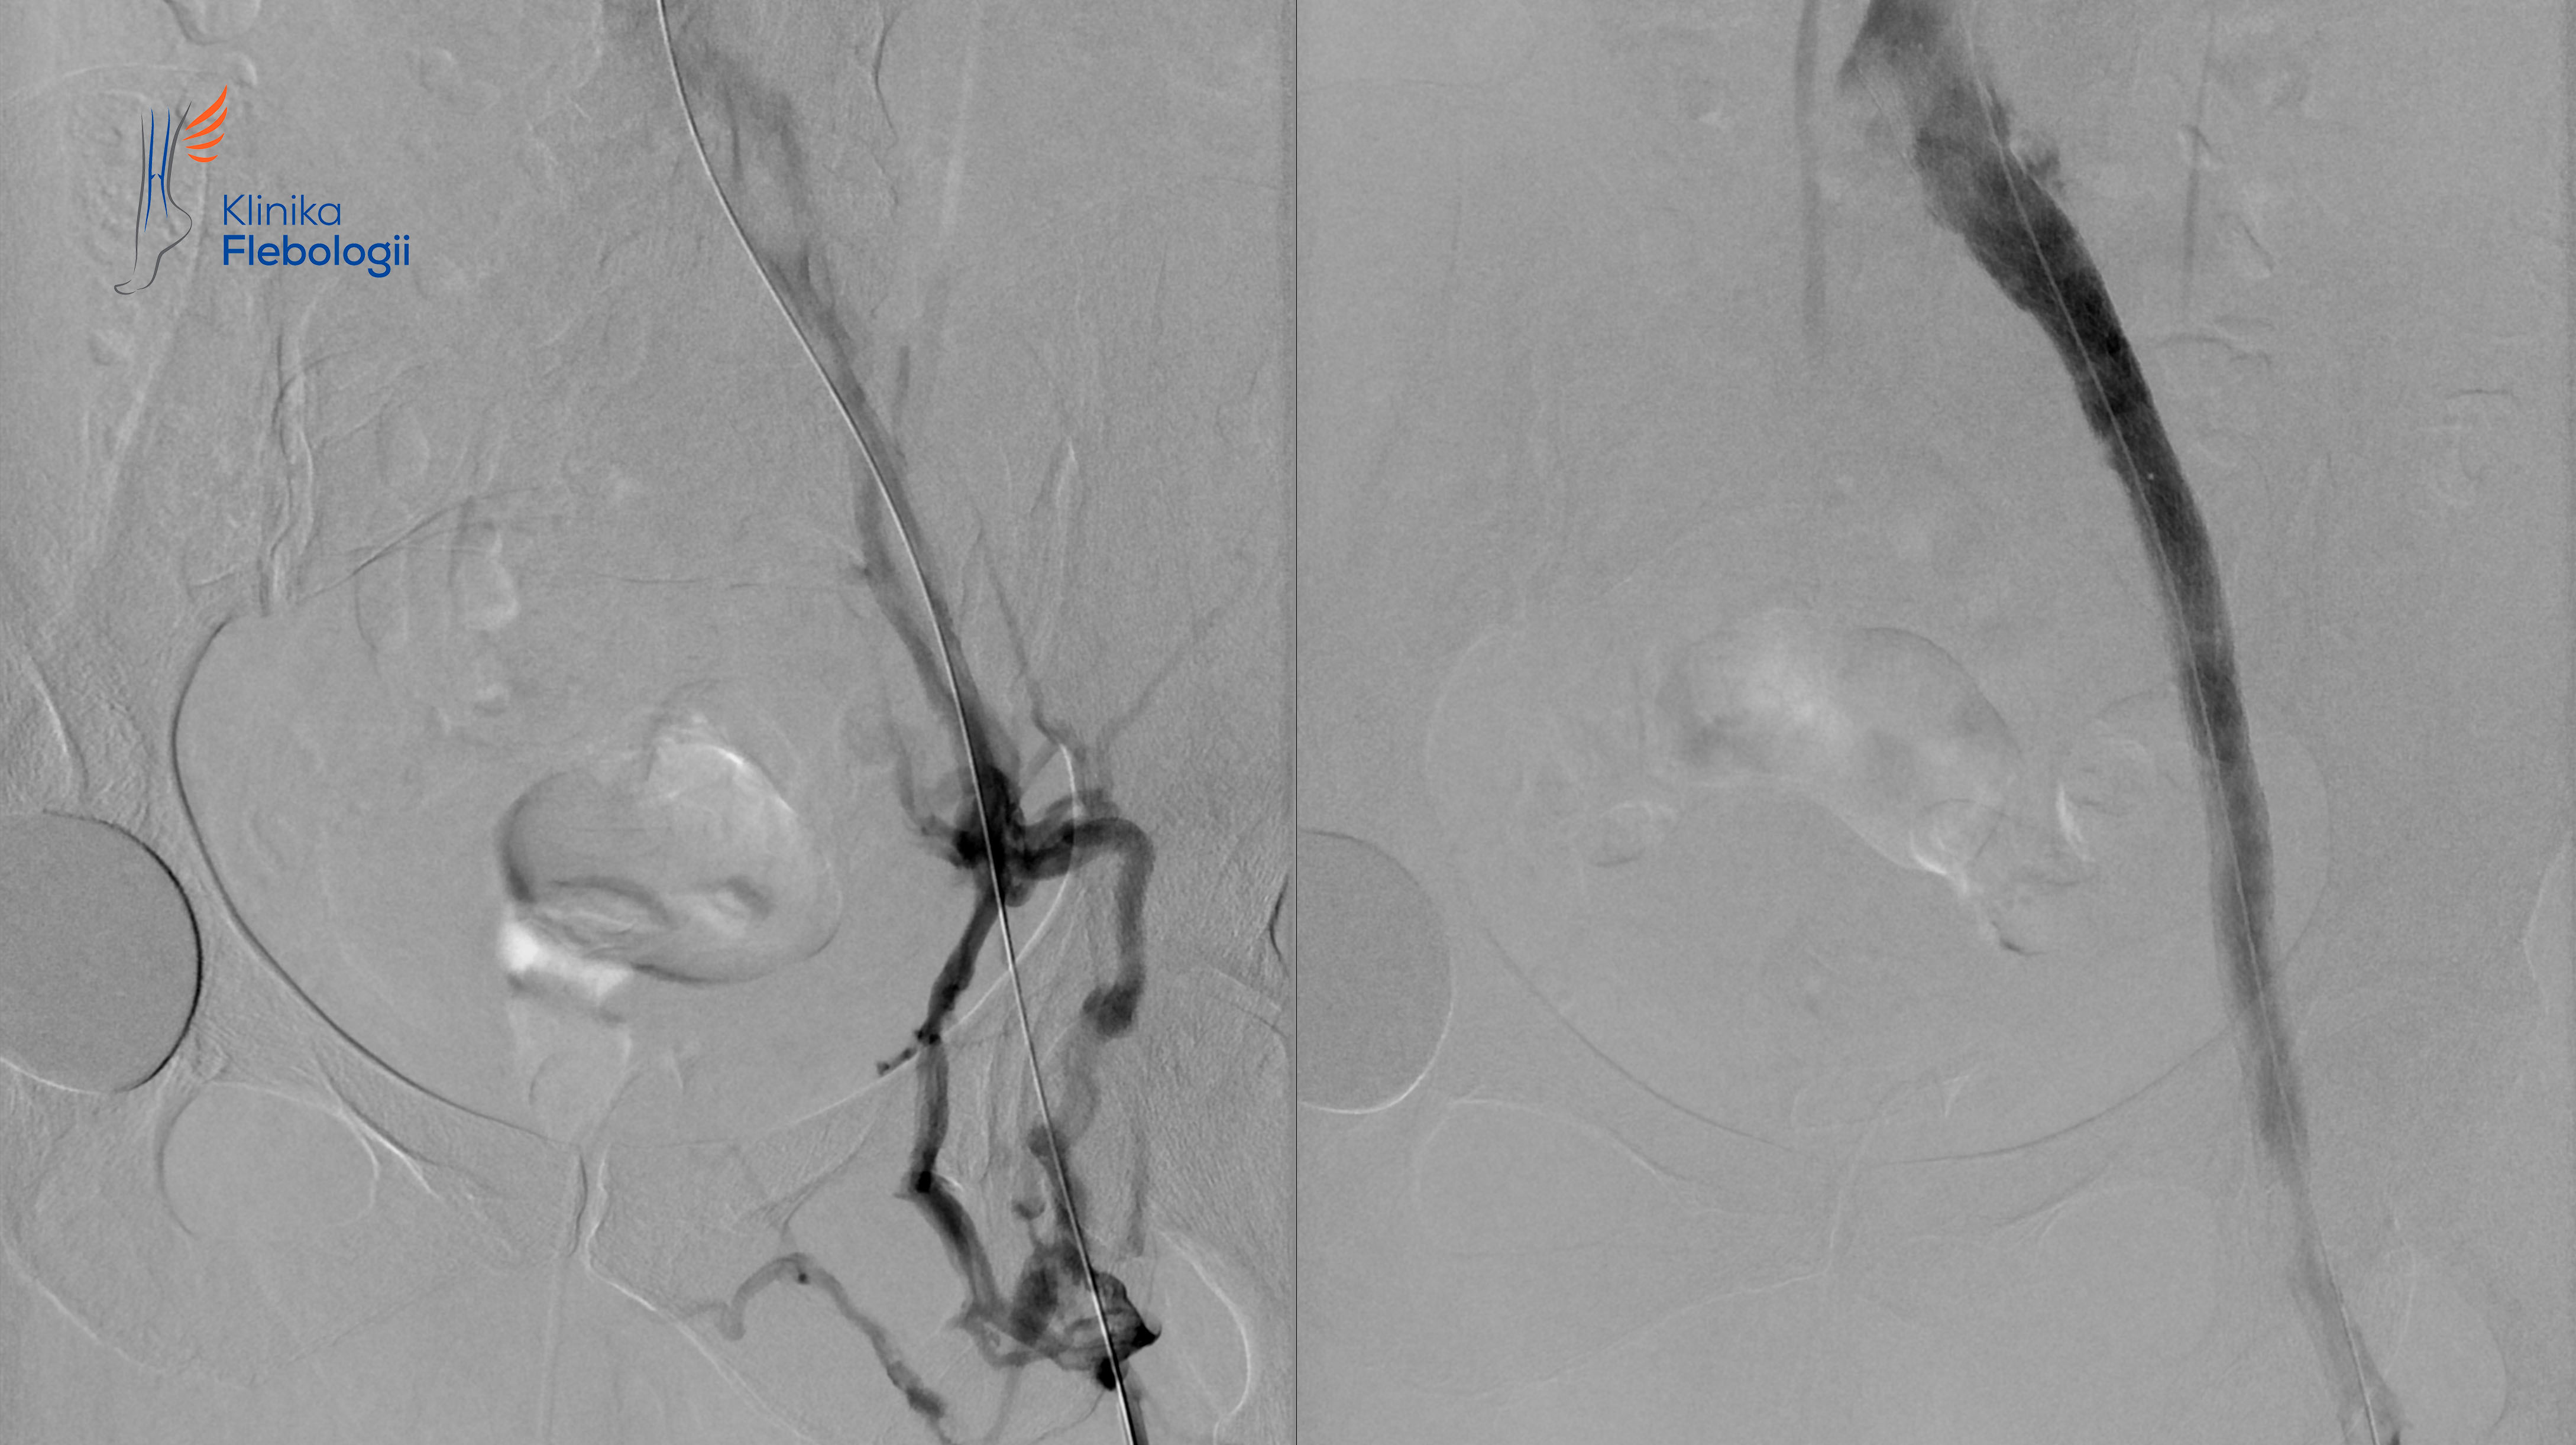

Zespół May-Thurnera. Stentowanie.

Stan po stentowaniu lewego spływu biodrowego w przebiegu zespołu May-Thurnera.